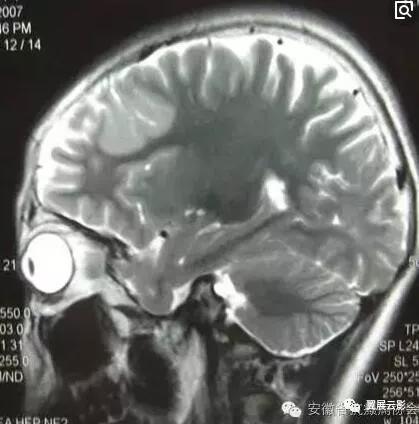

正常脑MRI——

正常脑组织在MRI像上,灰白质界限清楚,在T1WI上白质信号高于灰质,在T2WI上灰质信号高于白质,各脑叶,脑沟,脑裂,脑池及脑室形态自然,无变形及增大或缩小,各中线结构居中。